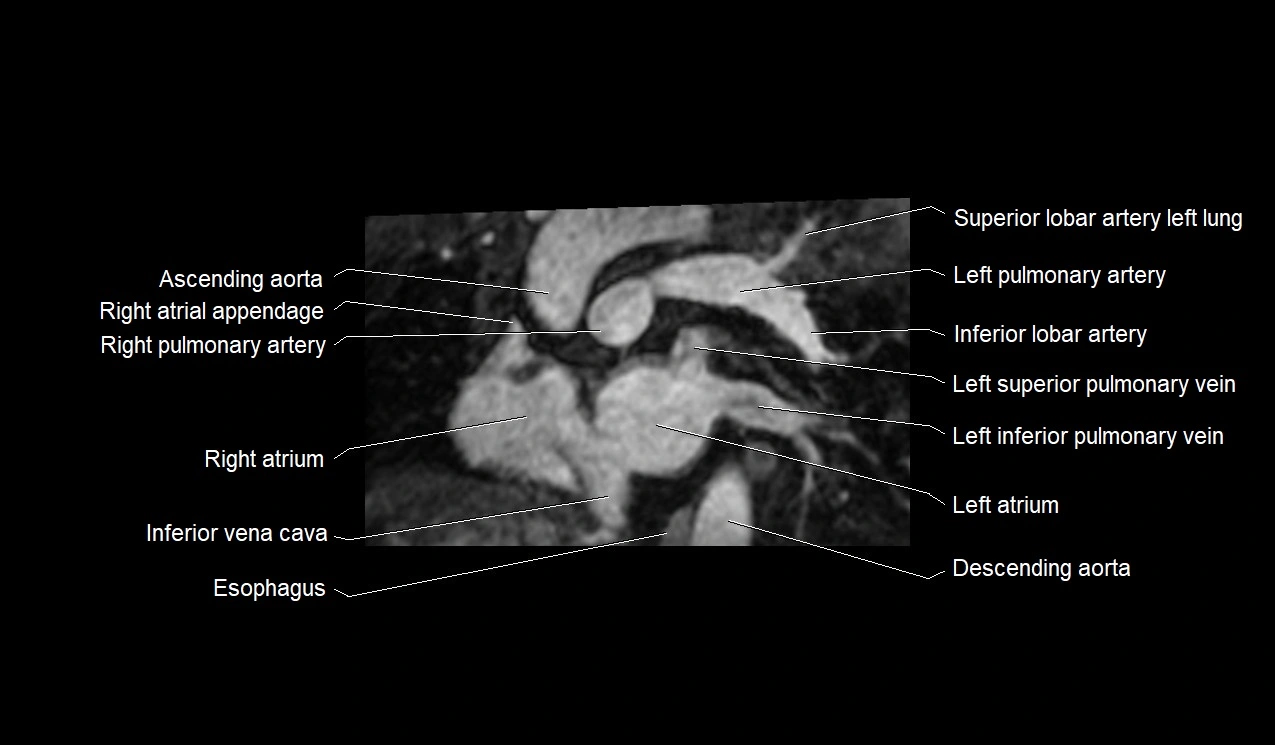

- Ascending aorta

- Left atrium

- Left inferior pulmonary vein

- Left pulmonary artery

- Left superior pulmonary vein

- Right atrium

- Right pulmonary artery